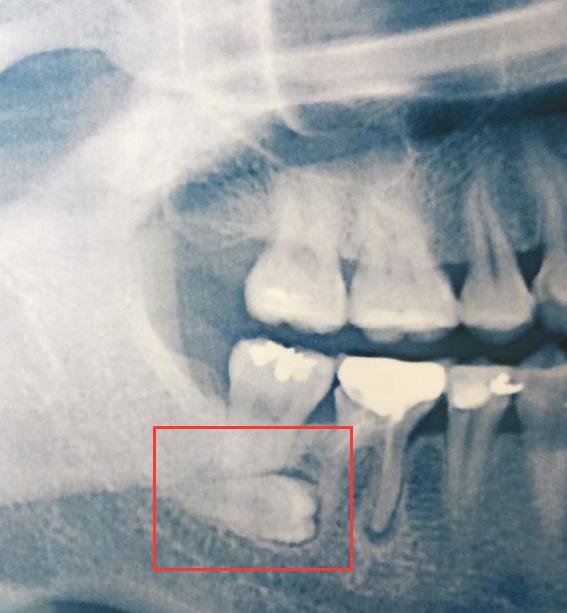

这几天,身边的好几个朋友都去看牙了。他们说 到了医院拍了个X光片,不拍不知道,一拍吓一跳,发现智齿要么躺着长,要么斜着长。

话说,智齿这样长在医学上叫阻生智齿,阻生牙不但会导致牙龈常常发炎,疼痛,还可能会引起邻牙蛀牙,牙根吸收,甚至松动。

高难度智齿

遇到这种智齿就得,拔!!对于那些不知道什么样的智齿该拔的同学,看下面:

3)阻生了,就是被前面牙挡住了,拔